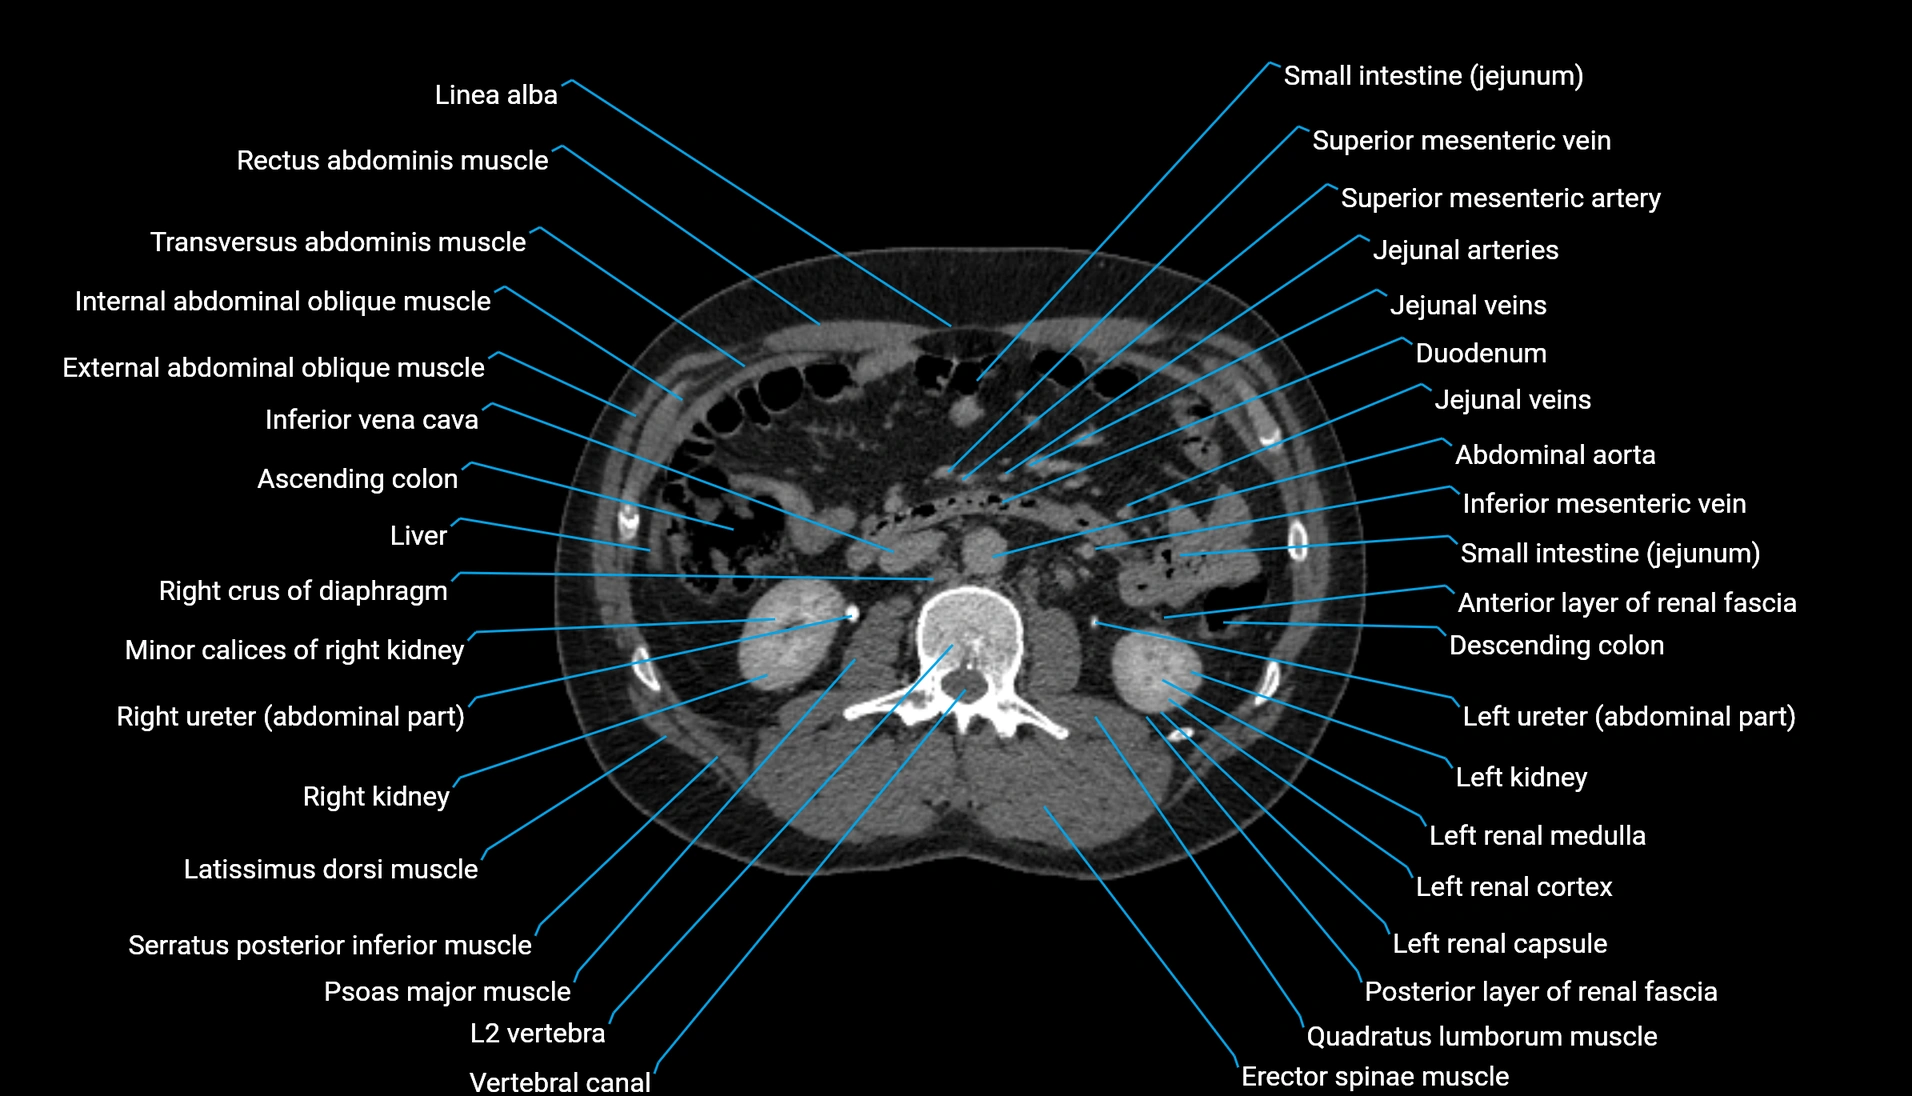

CT Appearance

Non-contrast CT:

-

Demonstrates cortical bone of acetabular rim in excellent detail

Detects fractures, dysplasia, retroversion, or bony overcoverage (pincer impingement)

3D reconstructions used in preoperative hip surgery planning

CT VRT 3D image

CT image